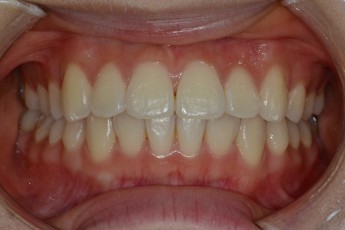

BEFORE & AFTER